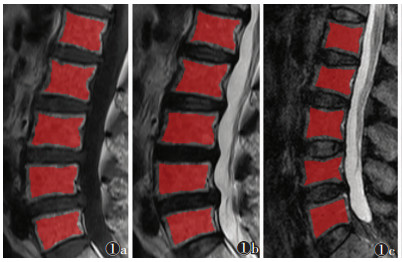

1.3 图像分析与纹理特征筛选将图像以DICOM格式从PACS导出至MaZda 4.6软件(http://www.eletel.p.lodz.pl/mazda/)。由2位具有5年以上影像诊断经验的医师协商后沿椎体边缘共同绘制ROI,ROI为累及病变的所有椎体,选择矢状位T1WI、T2WI和T2-STIR序列的正中层面图像,避开皮质和椎基静脉丛且不包含腰椎附件(图 1,2)。提取灰度级直方图、绝对梯度、灰度游程矩阵、灰度共生矩阵、自回归模型和小波变换6类纹理特征。然后通过软件提供的费希尔算法(Fisher coefficient,Fisher)、分类错误率+平均相关系数算法(classification error probability and average correlation coefficients,POE+ ACC)、交互信息算法(mutual information coefficient,MI)3种方法对3个序列进行降维筛选,每种方法筛选出10个最优纹理特征参数。

| 注:患者,女,59岁。图 1a为勾画矢状位T1WI序列的ROI;图 1b为勾画矢状位T2WI序列的ROI;图 1c为勾画矢状位T2-STIR序列的ROI 图 1 腰椎多发性骨髓瘤的ROI绘制 |